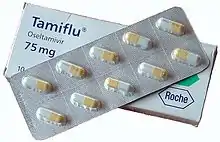

| Trade names | Tamiflu |

Oseltamivir, sold under the brand name Tamiflu, is an antiviral medication used to treat and prevent influenza A and influenza B (flu).[1] Some organizations recommend it in people who have complications or are at high risk of complications within 48 hours of first symptoms of infection.[5] They recommend it to prevent infection in those at high risk, but not the general population.[5] The Centers for Disease Control and Prevention (CDC) recommends that clinicians use their discretion to treat those at lower risk who present within 48 hours of first symptoms of infection.[5][6][7] It is taken by mouth, either as a pill or liquid.[1]

Oseltamivir was approved for medical use in the US in 1999.[1] It was the first neuraminidase inhibitor available by mouth.[17] It is on the World Health Organization's List of Essential Medicines but was downgraded to "complementary" status in 2017.[18][19] A generic version was approved in the US in 2016.[20][21] As of 2014, the wholesale cost in the developing world was about US$4.27 per day.[22] The wholesale cost for a course of treatment in the United States is about US$54.00 as of 2019.[23] In 2017, it was the 159th most commonly prescribed medication in the United States, with more than three million prescriptions.[24][25]

Oseltamivir is used for the prevention and treatment of influenza caused by influenza A and B viruses.[1][26] It is on the World Health Organization's List of Essential Medicines.[27] The WHO supports its use for severe illness due to confirmed or suspected influenza virus infection in critically ill people who have been hospitalized.[27] Oseltamivir's risk-benefit ratio is controversial.[9][10] In 2017, it was moved from the core to the complementary list based on its lower cost-effectiveness.[28] The Expert Committee did not recommend the deletion of oseltamivir from the EML and EMLc, recognizing that it is the only medicine included on the Model Lists for critically ill patients with influenza and for influenza pandemic preparedness.[18] However, the Committee noted that, since the inclusion of oseltamivir on the Model List in 2009, new evidence in seasonal and pandemic influenza has lowered earlier estimates of the magnitude of effect of oseltamivir on relevant clinical outcomes.[18] The Committee recommended that the listing of oseltamivir be amended, moving the medicine from the core to the Complementary List, and that its use be restricted to severe illness due to confirmed or suspected influenza virus infection in critically ill hospitalized patients.[18] The Expert Committee noted that WHO guidelines for pharmacological management of pandemic and seasonal influenza would be updated in 2017: unless new information is provided to support the use of oseltamivir in seasonal and pandemic outbreaks, the next Expert Committee might consider oseltamivir for deletion.[18]

In 1999, the FDA approved oseltamivir phosphate for the treatment of influenza in adults[69] based on two double-blinded, randomized, placebo-controlled clinical trials.[70] In June 2002, the European Medicines Agency (EMA) approved oseltamivir phosphate for prophylaxis and treatment of influenza. In 2003, a pooled analysis of ten randomised clinical trials concluded that oseltamivir reduced the risk of lower respiratory tract infections resulting in antibiotic use and hospital admissions in adults.[71]

Oseltamivir (as Tamiflu) was widely used during the H5N1 avian influenza epidemic in Southeast Asia in 2005. In response to the epidemic, various governments – including those of the United Kingdom, Canada, Israel, United States, and Australia – stockpiled quantities of oseltamivir in preparation for a possible pandemic[72] and there were worldwide shortages of the drug, driven by the high demand for stockpiling.[66] In November 2005, US President George W. Bush requested that Congress fund US$1 billion for the production and stockpile of oseltamivir, after Congress had already approved $1.8 billion for military use of the drug. Defense Secretary Donald Rumsfeld, who was a past chairman of Gilead Sciences, recused himself from all government decisions regarding the drug.[73]

Cost

As of 2014, the wholesale cost in the developing world was about US$4.27 per day.[22] The wholesale cost for a course of treatment in the United States is about US$54.00 as of 2019.[23] In 2017, it was the 159th most commonly prescribed medication in the United States, with more than three million prescriptions.[24][25]